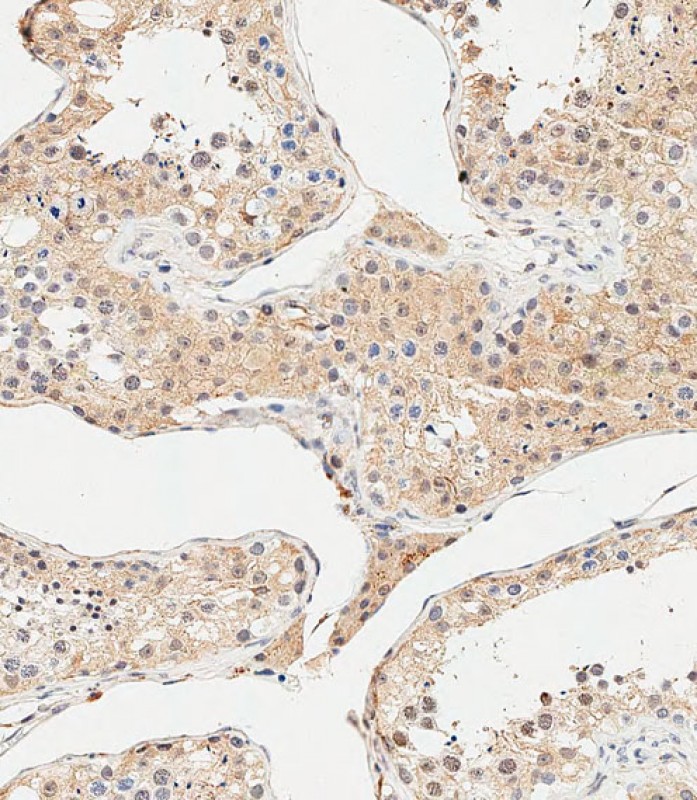

分类: 科研抗体货号: P34676别名: Stimulated by retinoic acid gene 8 protein homolog, STRA8 {ECO:0000312|EMBL:AAP471631}应用: WB,IHC反应种属: Human